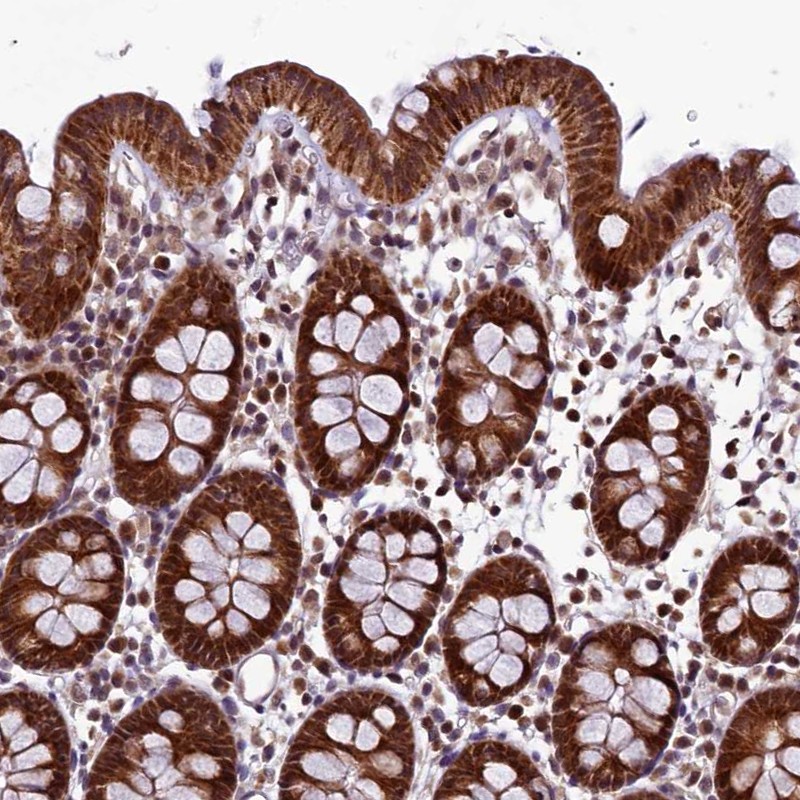

Immunohistochemical staining of human colon shows strong cytoplasmic positivity in glandular cells.